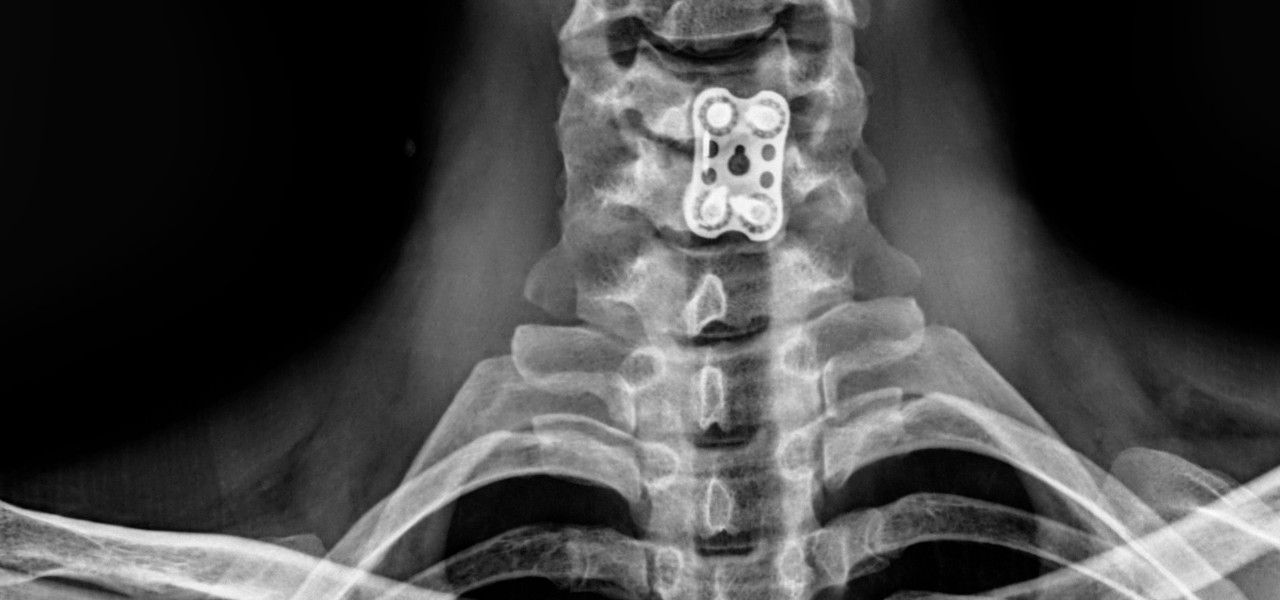

• Seguimiento post cirugía ortopédica

HumanosRadiología Digital Directa

Posteriormente la radiología computarizada evolucionó a la radiología digital directa en donde podíamos hacer placas radiográficas y ver las imágenes en aproximadamente 18-20 segundos después de tomar la radiografía, y esto fue un gran avance para la comunidad de médicos, veterinarios, antropólogos, restauradores, paleontólogos, investigadores, y gente que requería radiografías y que por la logística que se requería y lo que implicaba no utilizaba esta herramienta de diagnóstico. En la actualidad, en la era de la inmediateidad podemos tomar placas radiográficas de alta definición en 2-3 segundos, en lugares remotos, sin necesidad de energia electrica ya que los generadores de rayos X funcionan con baterías, así como los equipos de radiología digital directa, esto ha permitido que el servicio de radiología se pueda proporcionar en cualquier lugar donde se requiera, pudiendo llevarse a donde están los pacientes u objetos a radiografiar, con las ventajas que esto implica. Los equipos actuales son ligeros, portátiles, de alta frecuencia, de alta definición, se ha optimizado la radiación que generan, lo que permite obtener imágenes radiográficas de muy buena calidad, con técnicas radiográficas inferiores a lo que se requería con radiología análoga. Hoy en día manejamos radiología digital directa de alta resolución.

Ideal para pacientes con incapacidad para trasladarse al hospital o moverse. Fracturados, con fijación externa, osteoporosis, niños, adultos, pacientes geriatras, seguimiento post cirugía ortopédica.